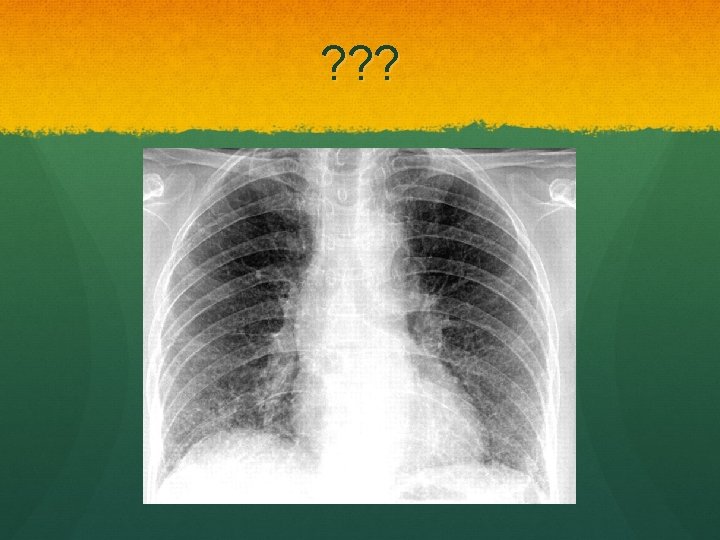

Coal Worker’s pneumoconiosis Dose dependent Simple Coal dust deposition in the lung Asymptomatic Diagnosis made by several small round opacities on CXR Caplan’s Severe disease may progress to progressive massive fibrosis

Progressive massive fibrosis Large round fibrotic nodules >10 mm Upper lobes Scarring Dyspnoea, cough, sputum May be black if cavitating lesions

PMF